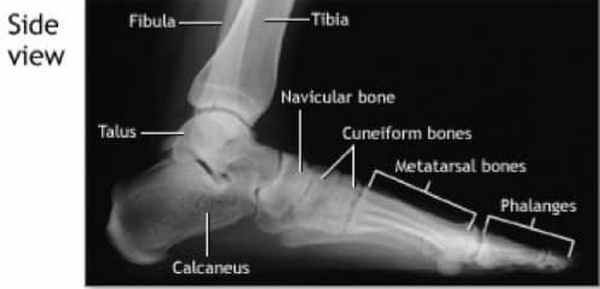

Рентгеновское изображение, относящееся к Метатарсалги

Рентгеновское изображение стопы - ФОТО WIKIMEDIA

- Рентген стопы, латеральный угол (при взгляде сбоку), на снимке мы видим большеберцовую кость (внутреннюю голень), малоберцовую кость (наружную голень), таранную кость (лодочную кость), пяточную кость (пятку), клинопись, плюсневую кость и фаланги (пальцы ног).